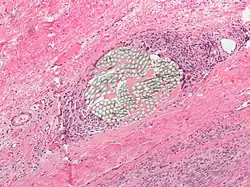

Giant cell arteritis

Giant cell arteritis,[6] also known as temporal arteritis or cranial arteritis, is the most common MGC-linked disease. This type of arteritis causes the arteries in the head, neck, and arm area to swell to abnormal sizes. Although the cause of this disease is not currently known, it appears to be related to polymyalgia rheumatica.[7]

The current highest standard for diagnosis is a temporal artery biopsy.[12] The skin on the patient's face is anesthetized, and an incision is made in the face around the area of the temples to obtain a sample of the temporal artery. The incision is then sutured. A histopathologist examines the sample under a microscope and issues a pathology report (pending extra tests that may be requested by the pathologist).